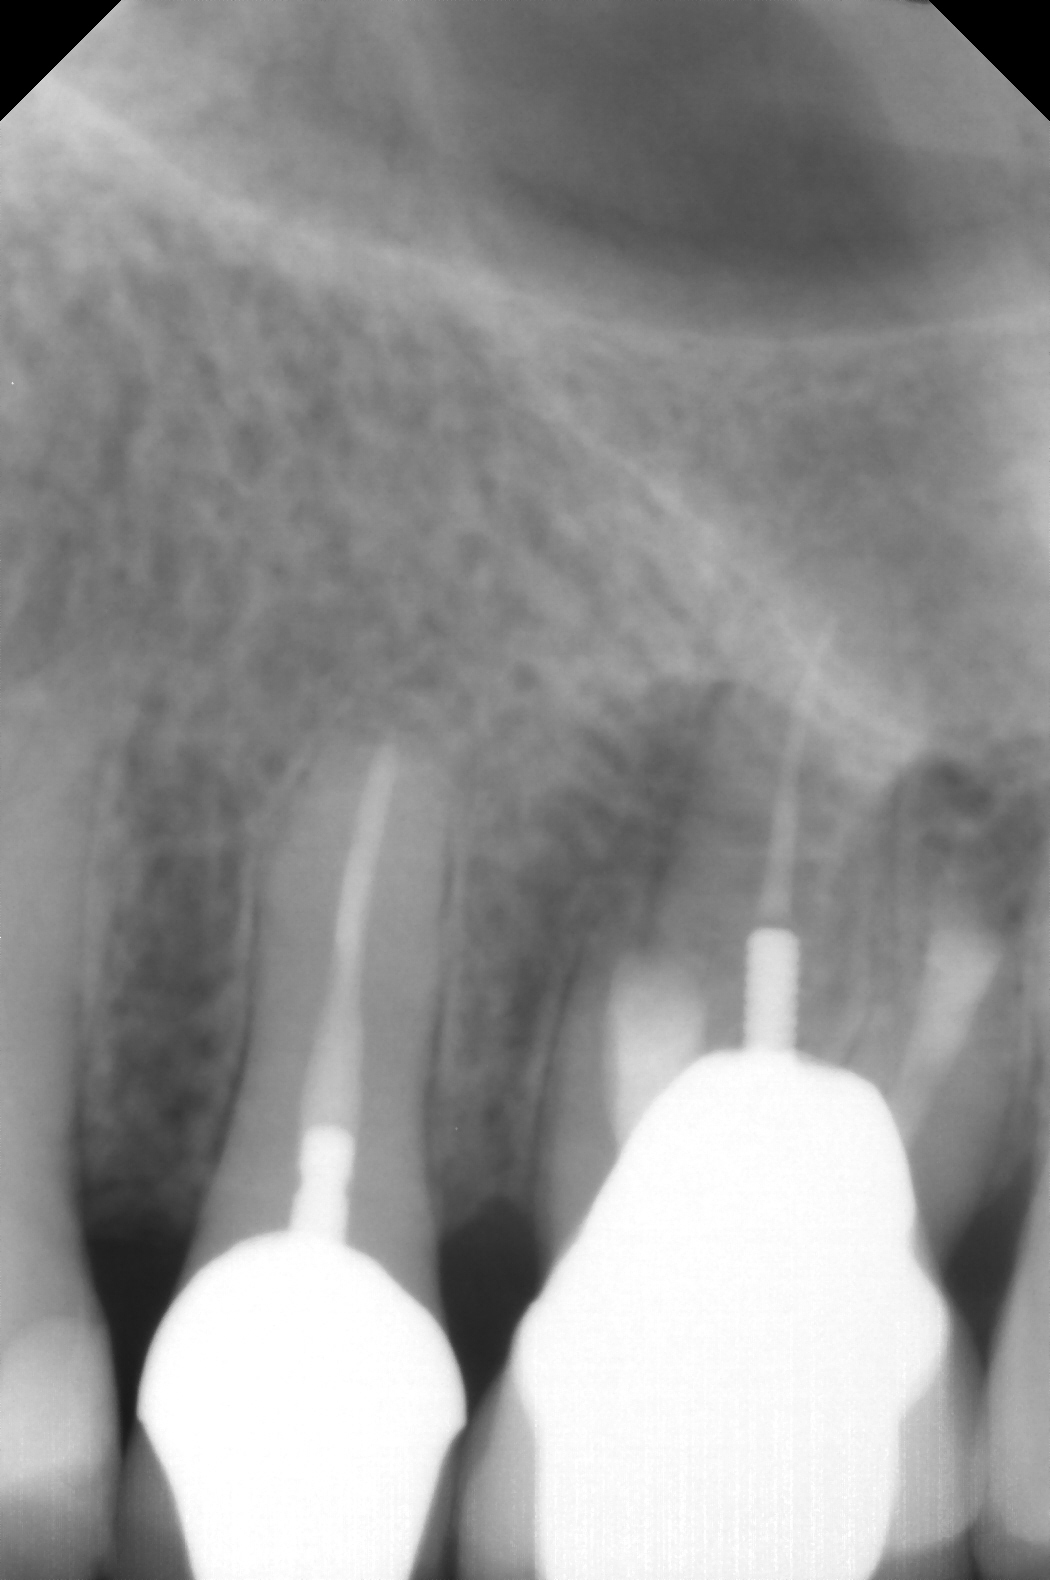

Fig 9 Preoperative radiographs showing mesial perforation.

Figure 9

Fig 10. Preoperative radiographs showing mesial perforation.

Figure 10

Clinical procedure: Once a perforation occurs, the extent of the perforation must be assessed. If there is an adjacent bony defect, the bony defect should first be filled with an osteoconductive or osteoinductive material. This can be done with a bone graft, calcium sulfate, or collagen/gelatin sponge. The dentinal portion of the tooth that has been perforated is then restored with MTA (Figure 9 through Figure 14).